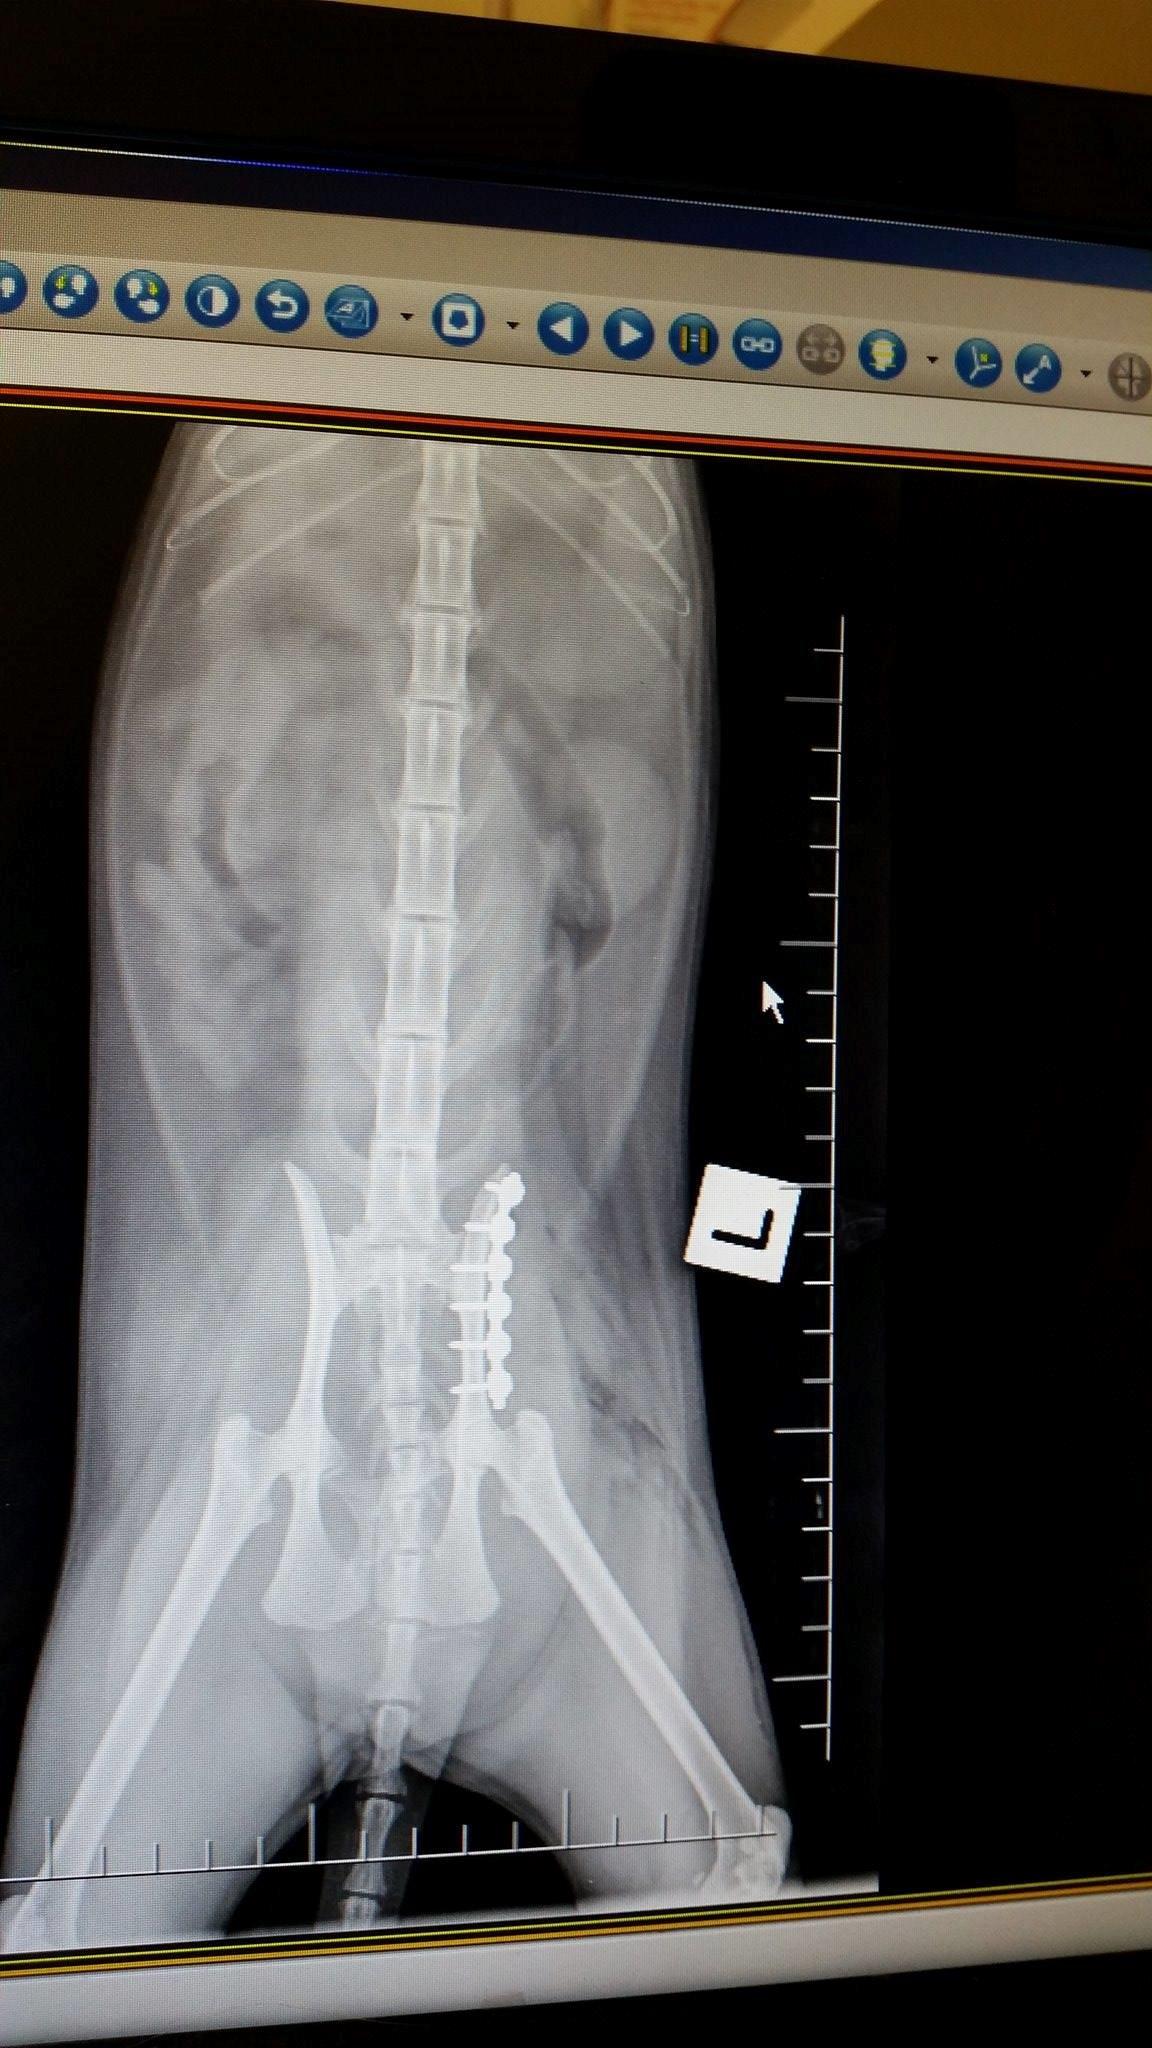

This evening, first working day of the week (Monday was Queen's Birthday weekend) I saw the surgeon. His name is David, and he put the x-rays up on screen again, and took me through the process of what would be done. She will have something called a 'string of pearls' which I visualise as a meccano piece with lots and lots of bolts. The bolts go into the bone, I guess they must be self-tapping. They hold the two slivers together.

He explained that so many days after the event (it will be nearly a week on Wednesday) all her muscles will have tightened and it will be very difficult to get the pelvis back to where it belongs; but he should at least be able to make a good job of widening the pelvis enough for faeces to go through it. See the x-ray attached, for what has happened. The pelvis has snapped off and shunted up forwards into the actual pelvis area.